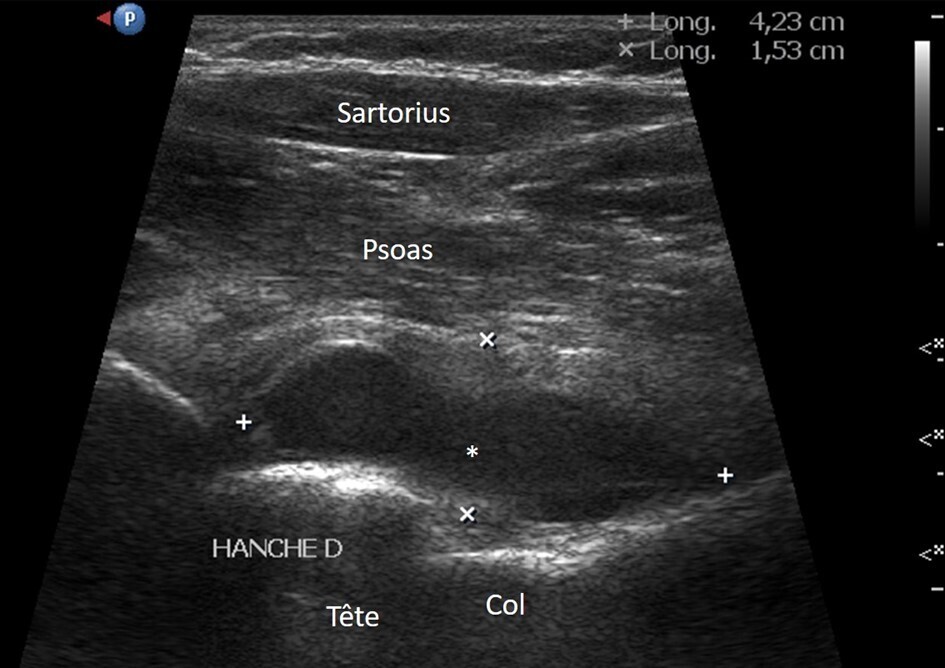

Épanchements articulaires et rhumatismes inflammatoires

L’échographie permet de détecter des épanchements articulaires parfois difficiles à mettre en évidence cliniquement. Elle est particulièrement utile pour évaluer des articulations profondes, comme la hanche ou l’épaule, pour lesquelles la palpation est limitée (fig. 2). Elle peut aussi guider la ponction. En évaluant la synoviale, la vascularisation synoviale et la présence d’épanchement intra-articulaire, l’échographie est aussi un outil de choix pour le diagnostic précoce des arthrites inflammatoires, en particulier la polyarthrite rhumatoïde. Elle permet de visualiser l’inflammation synoviale et d’identifier des signes d’activité inflammatoire, tels que l’hypervascularisation, qui sont des indicateurs importants pour évaluer l’évolution de la maladie et l’efficacité des traitements. L’échographie constitue ainsi une aide précieuse pour le diagnostic et pour l’évaluation des rhumatismes inflammatoires.3